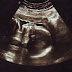

Baby boy will be joining our family sometime around March 13th. Stay tuned to learn more about our journey through infertility and pr...